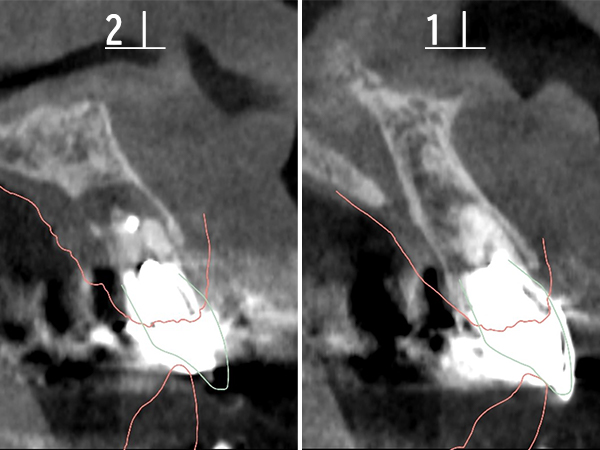

CTによるシミュレーション

2|

|1

1次手術手術後のレントゲン写真

2|

|1

レントゲン写真による評価